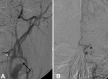

Figure (4):

Figure (4):. Patient post treatment with (A) ICA stenting (arrow) and (B) thrombectomy of the MCA (arrowhead), showing an evidence of recanalization of both arteries